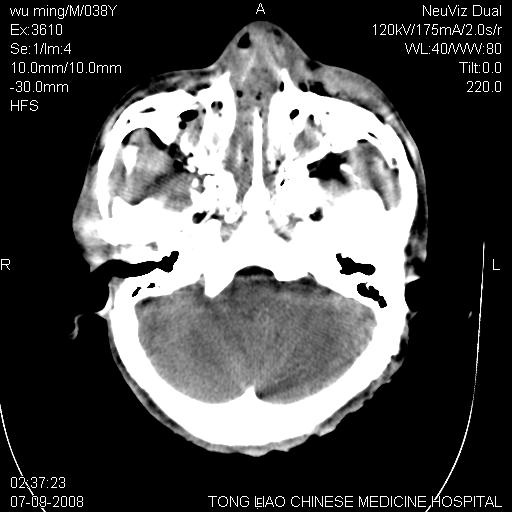

标题: CT14544:患者5楼坠下15分钟后CT扫描,2小时后死亡,请战友指 [打印本页]

标题: CT14544:患者5楼坠下15分钟后CT扫描,2小时后死亡,请战友指

考虑:面骨、颅底骨多发骨折,颅内高压(脑肿胀)。

面骨、颅底骨多发骨折,右侧硬膜下小血肿,弥漫轴索损伤,死亡原因可能是多种因素致。

1)颅底骨及颌面骨多发性骨折。2)副鼻窦及双侧鼻腔积血。

颅底骨折,窦腔内积血。考虑死亡原因为脑水肿压迫脑干或因大量失血死亡。

前颅窝颅底骨折,死的原因应该从头部来看不用说就是重度颅脑损伤。